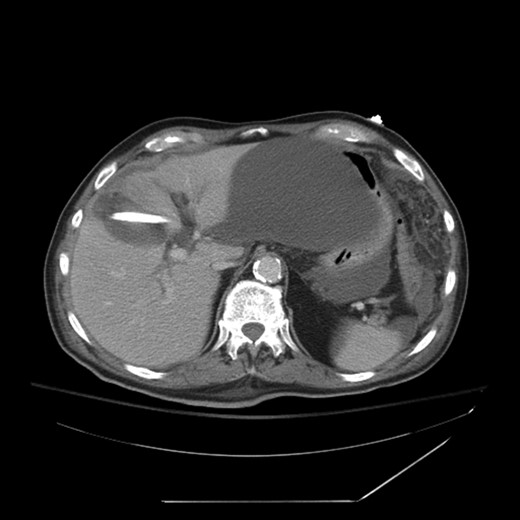

Postoperatively, the patient had persistent high-output bilious drainage. He was discharged on postoperative Day 6 with a drain in place. He returned to the outside facility approximately 4 days later with jaundice, weakness, fatigue and pain. A computed tomography (CT) scan of the abdomen and a nuclear cholescintigraphy scan confirmed a biliary leak with free intra-abdominal fluid consistent with biliary peritonitis (Fig. 1). The patient was transferred to our critical care unit for further management.

CT showing large biloma and intrahepatic biliary dilatation. Percutaneous drain visible in the gallbladder fossa.